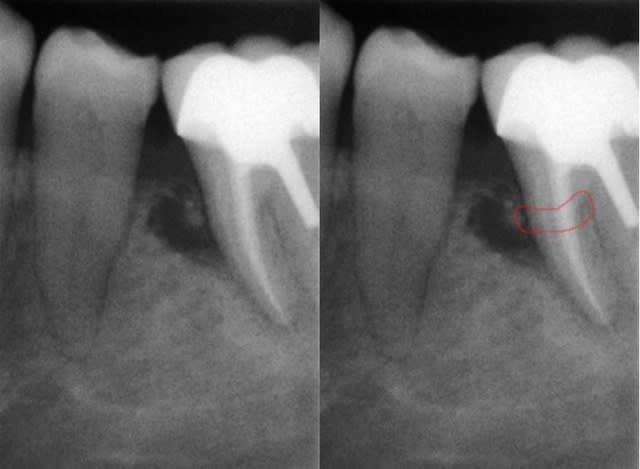

J'ai réalisé une endo sur la 36 début 2015 afin de réaliser un tfm et une coiffe ccm.

J'ai posé cette dernière il y a environ 3 mois et aujourd'hui j'ai revu la patiente qui se plaint d'une gêne à la gencive sans vraiment parler de douleur;

Je vous fais passer la radio qui montre une image au niveau du septum 35 36 et je suis vraiment étonné qu'en l'espace de si peu de temps je puisse avoir une telle lésion.

D'après vous est-ce un problème endo, paro (j'ai bien nettoyé l'espace aujourd'hui sous AL afin de vérifier l'absence d'un fragment de ciment de scellement mais rien de particulier).

> La fracture parait s'imposer comme une évidence.

Peut-être, mais typiquement les fractures( et fêlures) donnent des lésions en "doigt de gant" : elargissement au niveau desmodontal remontant jusqu'à la surface, et ce n'est pas le cas ici. En plus le délais semble court, pour une telle lésion consécutive à fracture, et pas de douleur à la pression(?).

Merci pour vos avis,en grossissant la radio on peut effectivement penser à une fracture de la racine.Ce n'est pourtant pas la racine qui supporte le tenon.